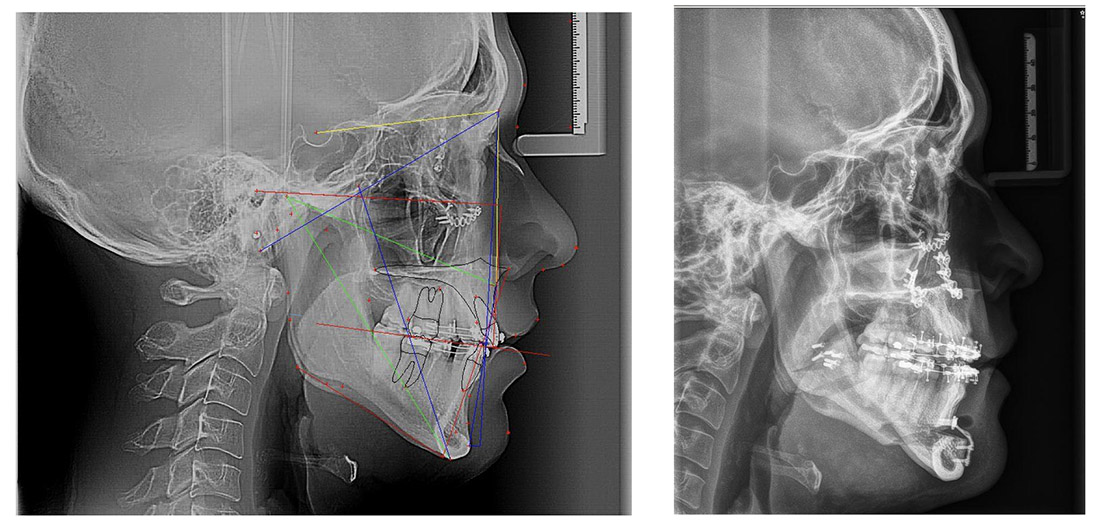

Cirugía ortognática

Es la corrección de la posición anómala de los maxilares mediante un proceso quirúrgico guiado por computador. Este tipo de procedimiento es llevado a cabo previo a una evaluación completa de forma multidisciplinaria en una clínica que brinda seguridad absoluta a los pacientes. Por último esta cirugía no genera ningún tipo de cicatriz y puede hacerse de forma ambulatoria.